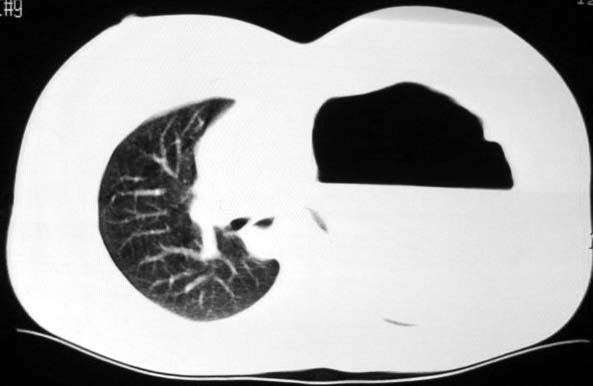

标题: CT5517:女性、24岁,反复胸痛、气促不能平卧半月。 [打印本页]

标题: CT5517:女性、24岁,反复胸痛、气促不能平卧半月。

左肺可见二个含气或液气的囊状影,左肺段支气管、左肺动脉显示不清,纵隔右移,考虑:左肺支气管肺囊肿,左肺发育不良,纵隔疝。

左侧气液腔与胃腔影相连,考虑膈疝。钡餐检查有助于诊断。

我看这是膈疝,在纵隔窗第六\\七幅图像上可见胃粘膜影,再者可见两个腔影,这在液气胸是不会有的.

液气胸 怎么会有2 个大腔?

左肺发育不良、支气管囊肿 应该纵隔左移的多吧

还是个膈疝